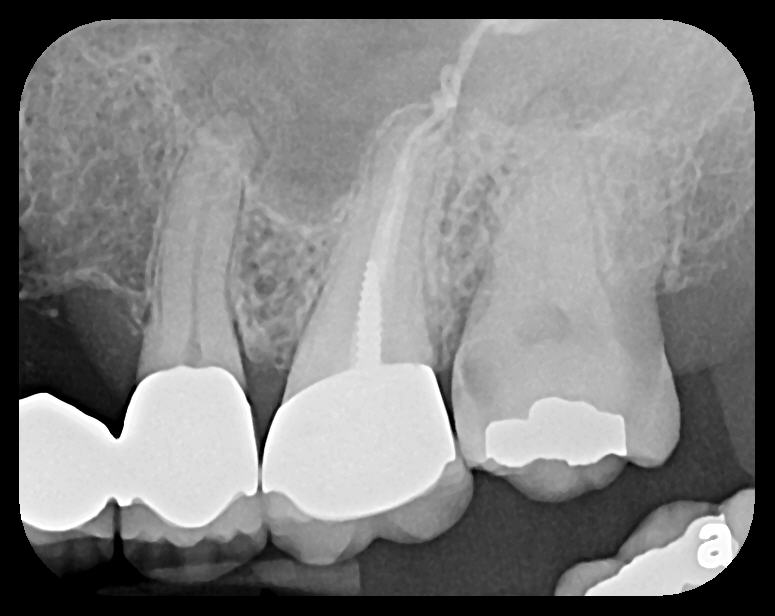

PSP sensor technology offers many advantages to the clinician in patient retention and workflow. The most important consideration is patient comfort and cooperation. PSP sensors are wafer-thin and flexible to allow placement in positions to capture third molar images without gagging or pain. The larger surface area of the most popular no. 2 size PSP sensor allows images of more dental anatomy (Figure 3); therefore, fewer exposures are necessary to create a full-mouth radiographic series. Their flexibility allows placement around tori and exostoses.1,9-12 The bite blocks, stabilizers, BW tabs, and positioning rings that were used for film radiographs will easily accommodate PSP sensor placement.

Some representative radiographic PSP images are exhibited here for demonstration of the anatomy and pathology that can be visualized with this technology. Many of these images would not have been possible if HW technology were used (Figure 3 through Figure 8).

As displayed here, the 2D radiographic images in Figure 3 through Figure 8 can alert the clinician to the need for a further 3D CBCT analysis to properly ascertain the anatomy and extent of the pathology that is initially visible in the intraoral radiographs. Proper treatment or referral to the appropriate specialty practice can follow.5,6 No. 2 PSP radiographs, when used in a conventional full-mouth series of radiographs on a patient with a relatively complete dentition, will routinely allow visualization of the anatomy of third molars, mandibular canal, maxillary sinuses, full dental root morphology, and bone anatomy beyond the apices2,16,17 (Figure 9 and Figure 10).

Fig 3. Two PSP PA radiographs of mandibular teeth showing: left, the initial view

of molar area and suspected pathology surrounding impacted tooth No. 32; center,

subsequently exposed PA radiograph, placed more distally, demonstrates extent

of large cyst as well as entire tooth and root No. 32. Proper alert as to presence

of suspected cyst and appropriate referral for 3D CBCT study and surgical

enucleation was given to the patient. Right: Same radiograph as on the left, but

with lighter superimposed outline of the area that would be visible using an HW

sensor rather than a PSP sensor. The small area of pathology is likely obscured

because it is visually overlaid by the root of tooth No. 31. Neglect of this significant

pathology may have resulted.

Figure 3